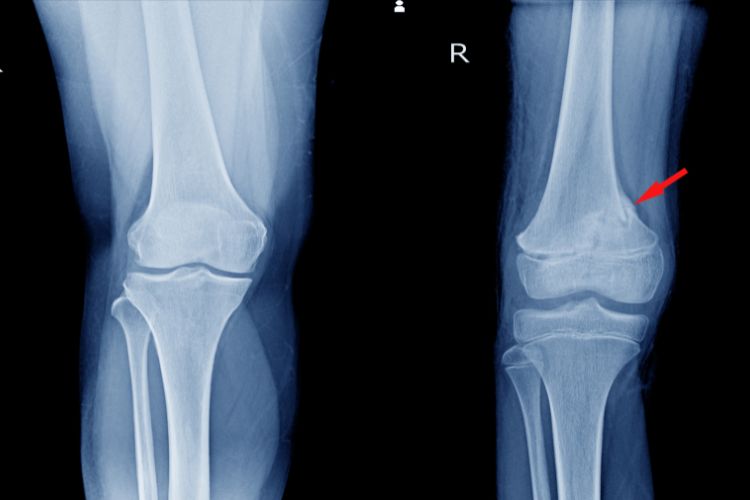

Magnetna rezonanca kolena pruža precizne snimke mekih tkiva i kostiju, omogućava rano otkrivanje oštećenja i bolesti, brza je, bezbolna i ne zahteva oporavak.